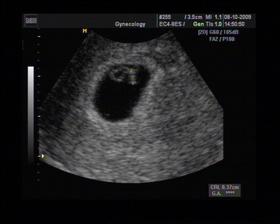

8/10 jsme se byli podívat u paní doktorky, zda testy nelhaly - a ono n e. Puclík měřil 0,37cm a co je důležité - srdíčko už funguje. Táta s Pepínem byli v ordinaci s námi, a když se na monitoru objevilo mimi, tak ho Pepíno pozdravil - udělal mu "ahoj" 🙂 oba nás to s Honzou dojalo. Další kontrola 22/10.